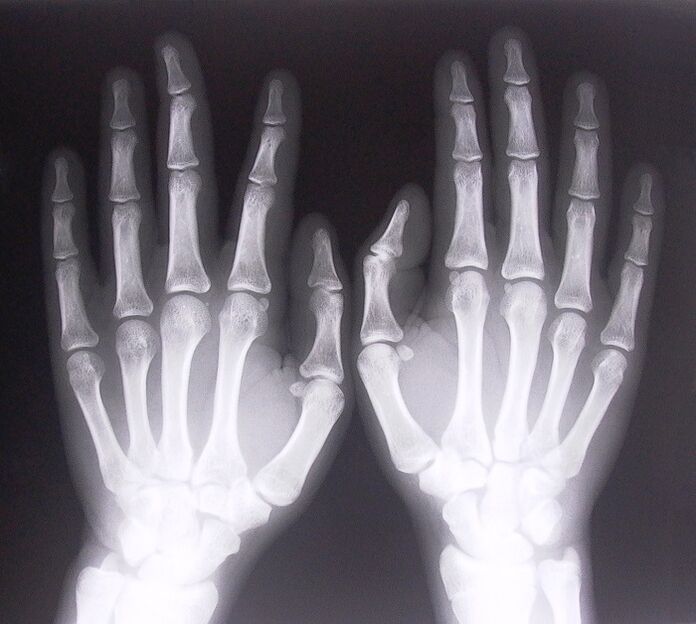

1. خذ الأشعة السينية.

الأشعة السينية كوسيلة لتشخيص الألم في مفاصل الأصابع